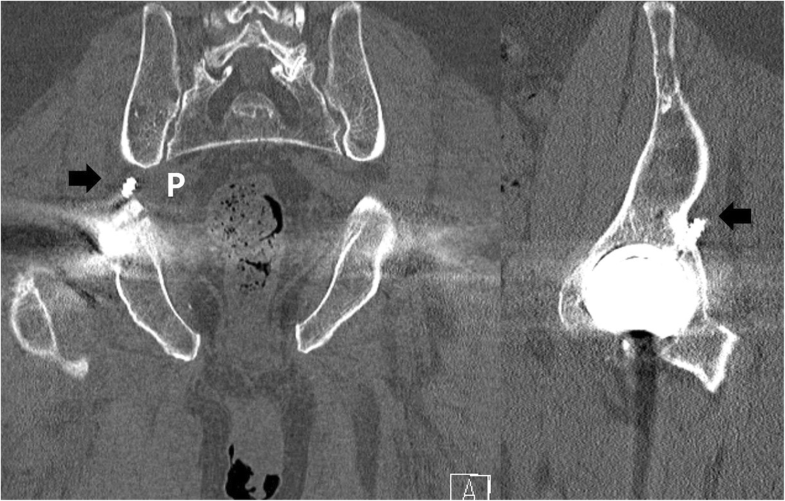

Endoscopic resection of acetabular screw tip to sciatic Endoscopic Decompression Of Sciatic Nerve The purpose of this study is to assess the effectiveness of endoscopic sciatic nerve decompression and evaluated the differences of. Sciatic nerve decompression is a treatment option for sciatic nerve pain that is caused by certain structural spinal conditions. Endoscopic decompression of the sciatic nerve appears useful in improving function and diminishing hip pain in sciatic nerve entrapment/dgs. Endoscopic sciatic. Endoscopic Decompression Of Sciatic Nerve.